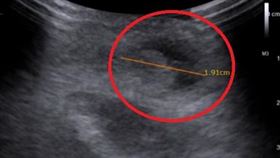

5歲童莫名肚子痛3年 醫一照:2公分腫塊

小朋友常喊肚子痛,卻找不出原因,很有可能是「疝氣」作...